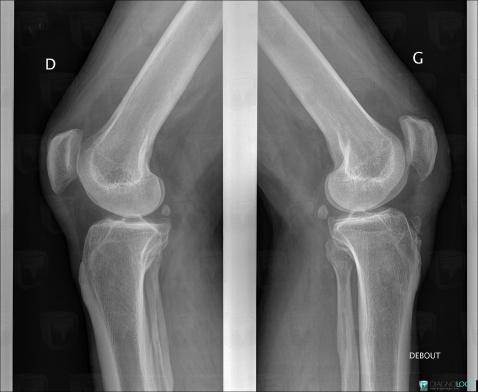

Maladie d'Osgood-Schlatter, Tibia -supérieur, Radio

- Diagnostic Maladie d'Osgood-Schlatter, Localisation(s) Tibia - 1/3 supérieur, comportant les gammes